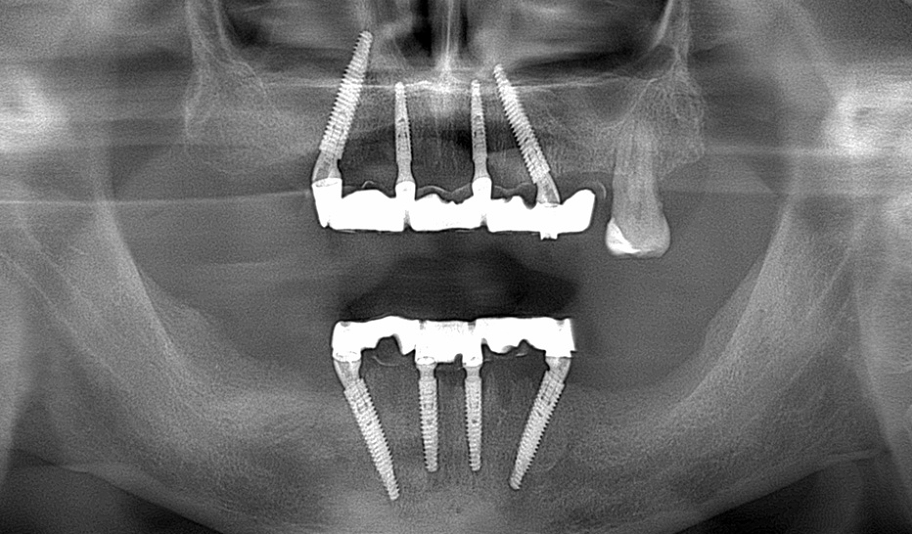

All on 4 NeoDentПроблемаТотальне руйнування та відсутність усіх зубів

РішенняІмплантація по системі All on 4 за допомогою імплантатів NeoDent

Термін лікування2 тижні